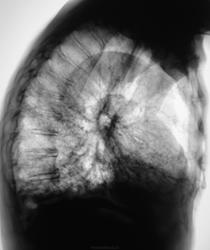

Это конечно шутка, а на самом деле здесь пневмония на фоне порока развития правого легкого. Справа внизу множественные ячейки. Ну и последствия травмы справа. Пневмония, думаю - дело временное.

Типа «сотовое лёгкое»? Нет? интересно, как оно выглядело до болезни?

Неоднозначно всё

Томограммы.

Диф Ds поликистоз

бронхоэктазы

пневмосклероз с развитем сотового лёгкого?

Пневмония (возможно грибковая)

Я никак не могу разглядеть просвет среднедолевого бронха, проходим ли он в должной степени? Очень интересно было бы посмотреть контроль

Конечно! Пациент в настоящее время находится в "общей терапии", интенсивно лечится, на контроль "даден" будет без сомнения, динамика будет выставлена.

Постараемся "чиркнуть" среднедолевой...